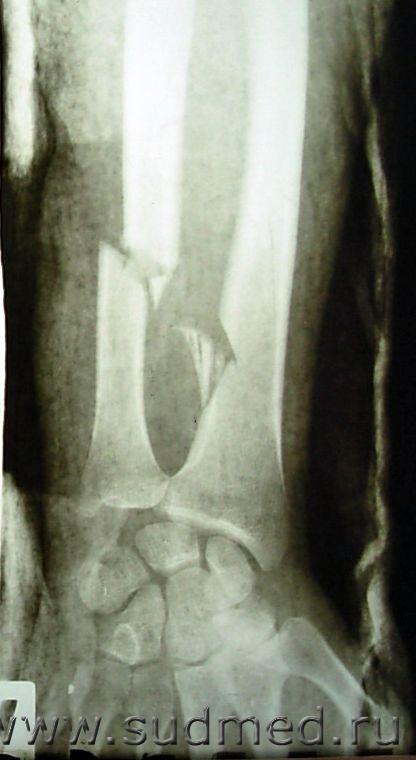

Суицидальная попытка в связи с болями в животе (мезентериальный тромбоз).

Судебная медицина - Прикрепленное изображение Судебная медицина - Прикрепленное изображение